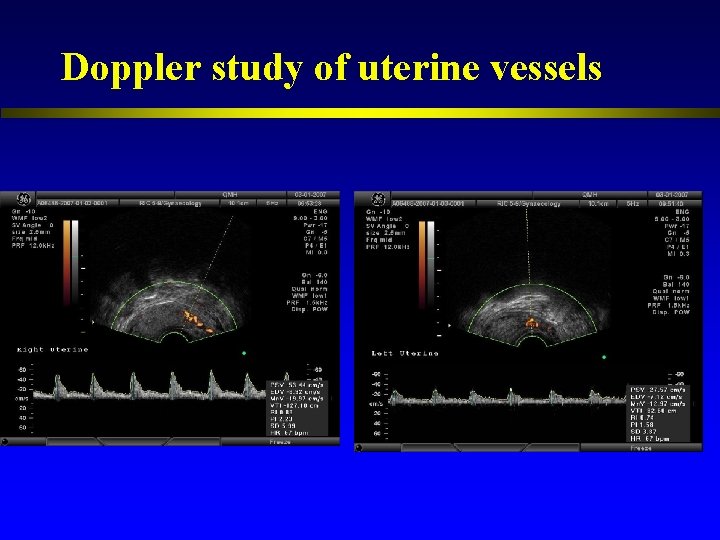

Doppler study of uterine vessels